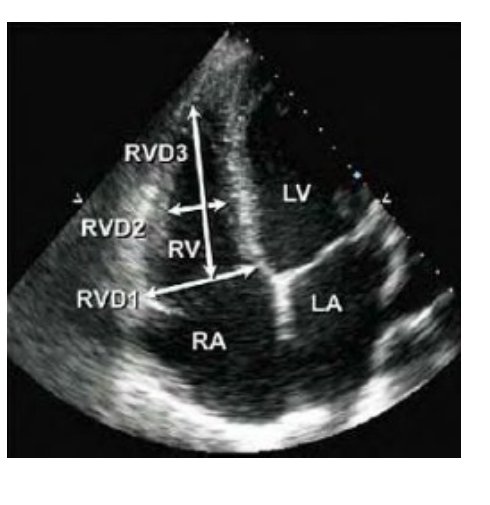

Right Ventricle Measurements Obtained from what view, at what cardiac cycle,

base diameter is made in where and tell me the way you would measure this?

The mid cavity diameter is made where and tell me how you would measure this?

abnormal Diameter is what number at the base and what number at the mid level what does this abnormal numbers indicated?

what is the abnormal longitudinal dimension?

Obtained from an Apical 4 chamber view at end diastole.

Base diameter is made in the RV near the TV insertion inner edge to inner edge

Mid cavity diameter is made at the level of papillary muscles inner edge to inner edge

Abnormal Diameter is > 4.1 cm at the base and

> 3.5 cm at the mid level

(indicates RV dilatation)

Abnormal longitudinal dimension is > 8.3 cm